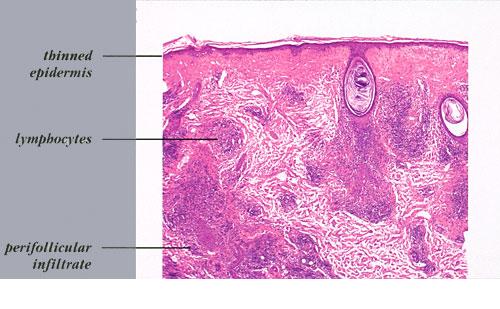

Discoid LE= الذئبة الحمامية القرصية